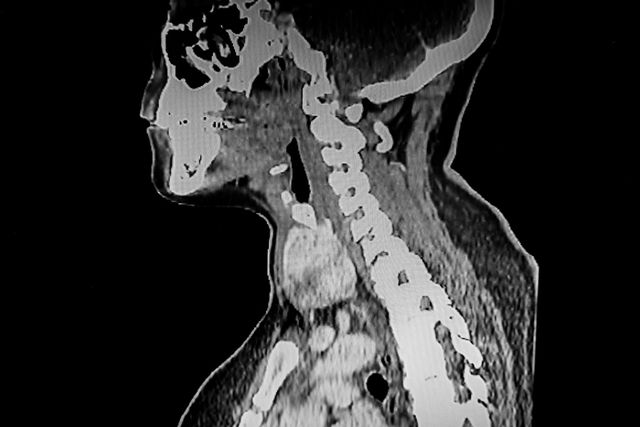

기사의 이해를 돕기 위한 사진 / Jo Panuwat D-shutterstock.com

진단은 초음파와 세침검사로 진행갑상선암은 일반적으로 초음파 검사를 통해 결절을 확인한 후, 세침흡인검사라는 방식으로 조직을 채취해 악성 여부를 진단한다. 검사 방법은 비교적 간단하며, 국소마취 없이 외래에서 시행할 수 있다.

초음파 결과만으로도 양성인지 악성인지 어느 정도 구분이 가능하며, 필요할 경우 혈액검사, CT, MRI 등을 추가로 시행하기도 한다. 갑상선암은 비교적 조기에 진단이 가능하지만, 정확한 판단을 위해 여러 검사를 병행하는 것이 중요하다.